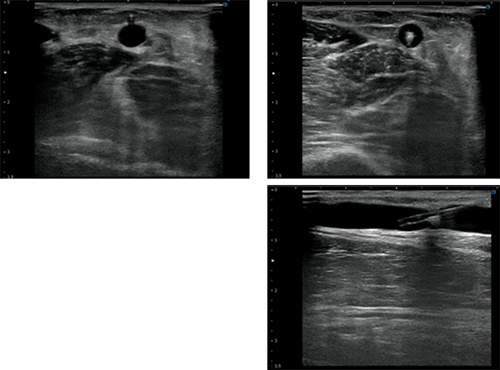

プローブは、アプローチする血管を輪切りとする短軸像で、血管の径・深さおよび走行を確認します。その際、血管が画面中央を維持できるようにします。走査(スキャン)は、アプローチする血管走行が真っ直ぐであるか、蛇行や分岐などがないか確認するために行います。

次に、血管を縦切りとする長軸像で、血管が急に深く潜っていたり、浅くなっていないかを確認します。

実際の穿刺は、アプローチする血管が画面の中央になるように短軸像でプローブを当て、プローブの中心線から針を刺入します。プローブを針に対して直角に当てると針と血管の走行が一致しているか否かを判断しやすくなります。

ビームを針先の先端に置きながら針を進めていき、画面上で針が白く映ったらいったん止めます。血管の中央上部に針先があることをシャフトの描出により血管走行と針の方向が一致していることによって確認し、プローブを進行方向に送ります(写真2)。

写真2 血管エコーの進め方

この一連の動作を繰り返し、血管内まで針先が進んだら針を徐々に倒しながら穿刺針の外筒部分が血管内に入るまでしっかりと進めます。

最後に、針先先端を上下左右に動かし血管壁に針先が引っかかっていないかを確認します。